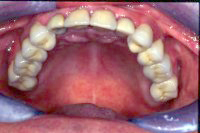

Und schliesslich geht es in der Zahnprophylaxe immer auch darum, den Zustand nach einer Zahnsanierung durch entsprechende individuelle Informationen und Instruktionen gesund zu erhalten wie das in den Abb. 2 und 3 gezeigt wird.